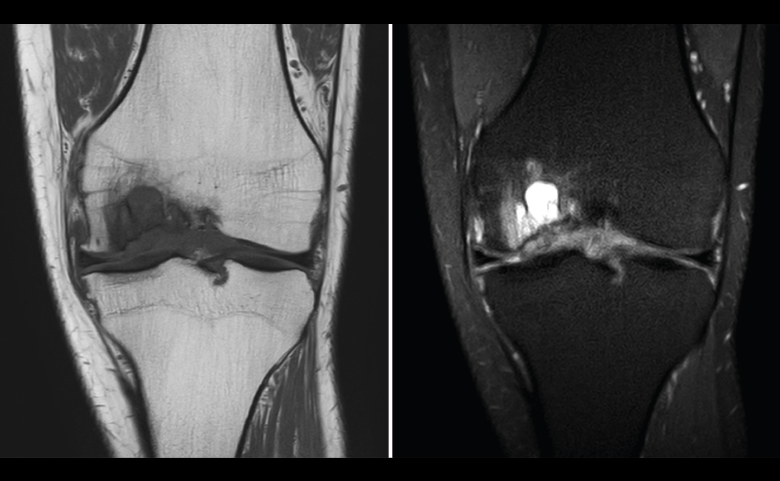

Figura 53. Corte de secuencia sagital (A) y axial (B) T2 Fat-Sat de RM de rodilla: lesiones osteocondrales en el fémur y la rótula.

Numerosos estudios demuestran la utilidad de la RM para definir la estabilidad o inestabilidad de la lesión en la osteocondritis, destacando su carácter no invasivo y la capacidad de valorar la progresión y la respuesta al tratamiento(21)(Figuras 53 y 54).

En la osteocondritis se aprecia una lesión subcondral caracterizada por resorción ósea, colapso y la formación de un secuestro.

El estudio por RM es una herramienta valiosa para diagnosticar e identificar las lesiones del cartílago. Conocer el aspecto del cartílago y saber cuánto y cuándo se lesiona, basándose en las clasificaciones actuales, permiten al radiólogo proporcionar la máxima información al clínico(20).